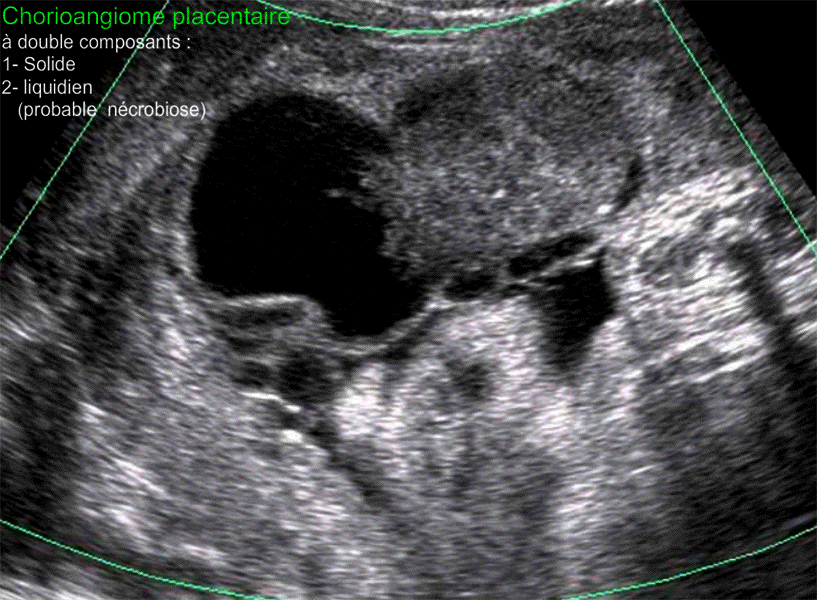

Images échographiques montrant un chorio-angiome placentaire découvert à 29 SA lors de la prise en charge d'une menace d'accouchement prématuré dans un contexte d'hydramnios sévère nécessitant l'évacuation de 2500 cc du liquide amniotique. Il s'agit d'un chorioangiome à deux composants, le premier est solide, bien vascularisé ; le seconde est liquidien dont la présence peut être expliquée par la survenue antérieurement d'une nécrobiose partielle par obturation de certains vaisseaux nourriciers de ce chorioangiome. Mise à jour : le 3 Décembre, 2020 |